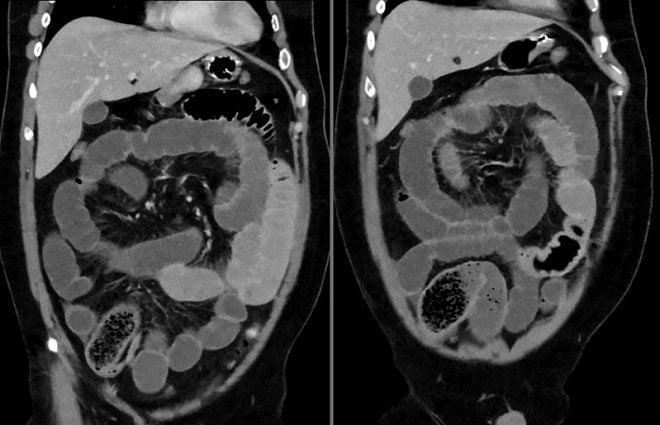

Verpleegkundigen en artsen ondersteunen bij de diagnostiek en behandeling van ileus in de palliatieve fase. Dat is het doel van een nieuwe digitale beslisboom, ontwikkeld door Integraal Kankercentrum Nederland (IKNL).